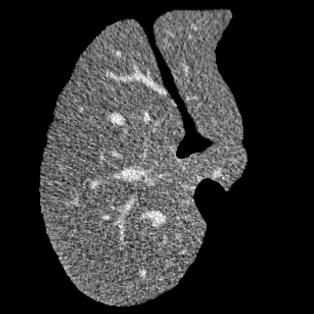

Manually segmenting the hepatic vessels from Computer Tomography (CT) is far more expertise-demanding and laborious than other structures due to the low-contrast and complex morphology of vessels, resulting in the extreme lack of high-quality labeled data. Without sufficient high-quality annotations, the usual data-driven learning-based approaches struggle with deficient training. On the other hand, directly introducing additional data with low-quality annotations may confuse the network, leading to undesirable performance degradation. To address this issue, we propose a novel mean-teacher-assisted confident learning framework to robustly exploit the noisy labeled data for the challenging hepatic vessel segmentation task. Specifically, with the adapted confident learning assisted by a third party, i.e., the weight-averaged teacher model, the noisy labels in the additional low-quality dataset can be transformed from "encumbrance" to "treasure" via progressive pixel-wise soft-correction, thus providing productive guidance. Extensive experiments using two public datasets demonstrate the superiority of the proposed framework as well as the effectiveness of each component.